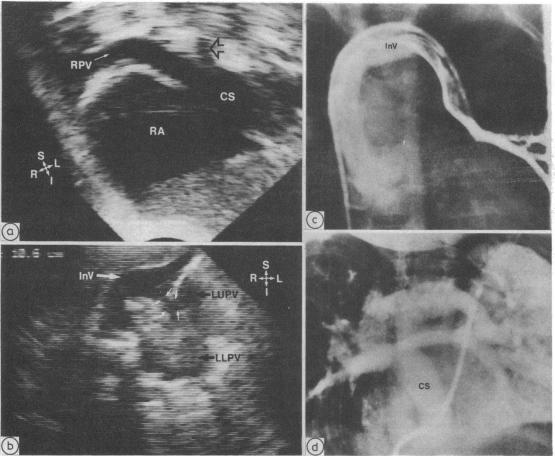

Total anomalous pulmonary venous connection can be diagnosed by cross sectional echocardiography. Information is, however, lacking concerning the diagnostic accuracy of this imaging method and any factors which may influence it. To predict the pulmonary venous connection 463 patients with congenital heart disease who had angiographic confirmation were prospectively examined. Total anomalous pulmonary venous connection was present in 34 (7%) patients and correctly detected in 33 (97% sensitivity). There were two false positive results (99% specificity). All 23 patients with atrial situs solitus with or without associated congenital heart defects were correctly detected. One false negative result occurred in a patient with right atrial isomerism and complex congenital heart disease with decreased pulmonary blood flow. Diagnosis of the type of total anomalous pulmonary venous connection, including the site and other anatomical details, was analysed and was correct in 24 of 34 (71%) patients. Errors included incorrect prediction of the site of total anomalous pulmonary venous connection in five patients with right atrial isomerism, atrioventricular canal defect, and pulmonary atresia, details of confluence interconnection in three of four patients with the mixed type of connection, undiagnosed pulmonary venous obstruction in three of the patients with right atrial isomerism, and failure to predict common pulmonary vein atresia in one patient. Factors which were related to incorrect echocardiographic diagnosis were abnormal atrial situs, mixed total anomalous pulmonary venous connection, and associated congenital cardiac defects, whereas age, weight, sex, clinical condition, and time during the study were not related. It is concluded that cross sectional echocardiography can be used to diagnose accurately total anomalous pulmonary venous connection. This method can be the definitive imaging and diagnostic method in symptomatic infants with total anomalous pulmonary venous connection who have atrial situs solitus, unifocal pulmonary venous connection, and no evidence of other major congenital cardiac defect.

完全性肺静脉异位连接可通过横断面超声心动图诊断。然而,关于这种成像方法的诊断准确性以及可能影响其的任何因素,目前尚缺乏相关信息。为预测肺静脉连接情况,对463例经血管造影证实的先天性心脏病患者进行了前瞻性检查。34例(7%)患者存在完全性肺静脉异位连接,其中33例(敏感性97%)被正确检测出。有2例假阳性结果(特异性99%)。所有23例心房正位且伴有或不伴有相关先天性心脏缺陷的患者均被正确检测出。1例假阴性结果出现在1例右心房异构且患有复杂先天性心脏病并伴有肺血流量减少的患者中。对完全性肺静脉异位连接的类型,包括部位及其他解剖细节进行了分析,34例患者中有24例(71%)诊断正确。错误包括:5例右心房异构、房室管缺损和肺动脉闭锁患者中完全性肺静脉异位连接部位预测错误;4例混合型连接患者中有3例汇合连接细节未被诊断出;3例右心房异构患者中有3例未诊断出肺静脉梗阻;1例患者未预测出共同肺静脉闭锁。与超声心动图诊断错误相关的因素为心房位置异常、混合型完全性肺静脉异位连接及相关先天性心脏缺陷,而年龄、体重、性别、临床状况及研究期间的时间与之无关。结论是,横断面超声心动图可用于准确诊断完全性肺静脉异位连接。对于有症状的完全性肺静脉异位连接婴儿,若其心房正位、肺静脉连接单一且无其他主要先天性心脏缺陷证据,该方法可作为确定性的成像和诊断方法。